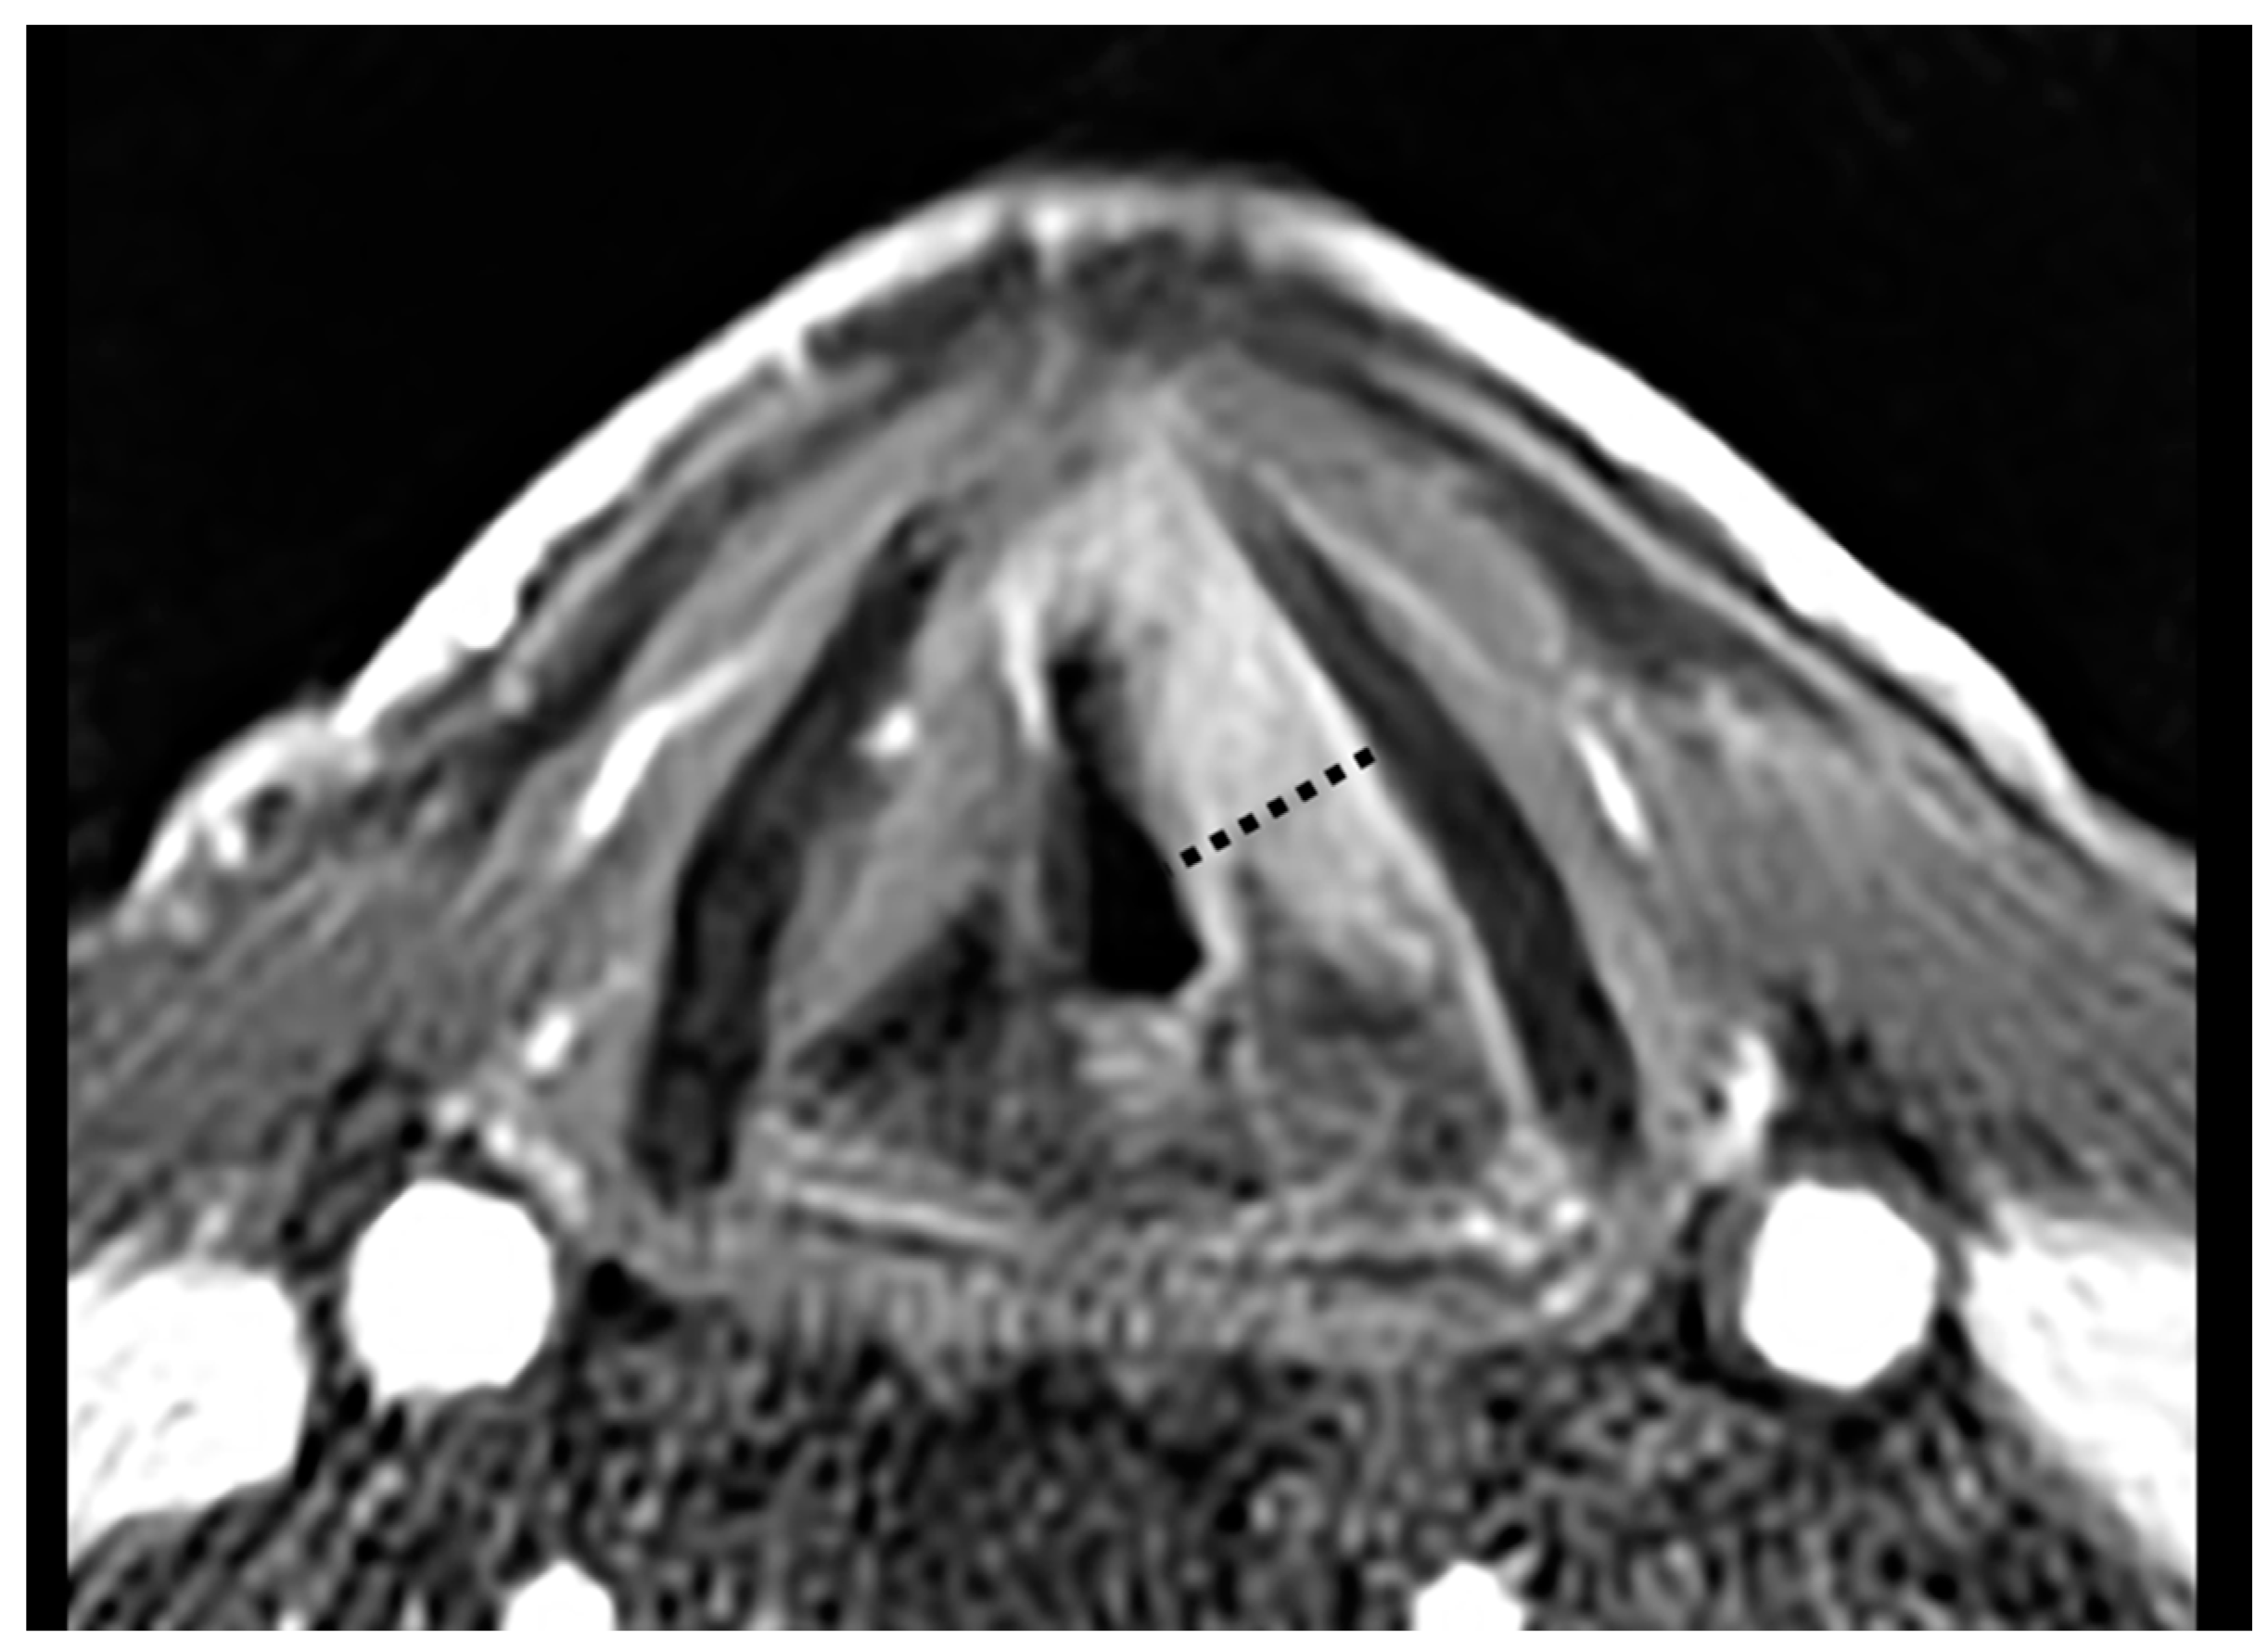

- Ravanelli, M.; Paderno, A.; Del Bon, F.; Montalto, N.; Pessina, C.; Battocchio, S.; Farina, D.; Nicolai, P.; Maroldi, R.; Piazza, C. Prediction of Posterior Paraglottic Space and Cricoarytenoid Unit Involvement in Endoscopically T3 Glottic Cancer with Arytenoid Fixation by Magnetic Resonance with Surface Coils. Cancers 2019, 11, 67. [Google Scholar] [CrossRef] [PubMed]